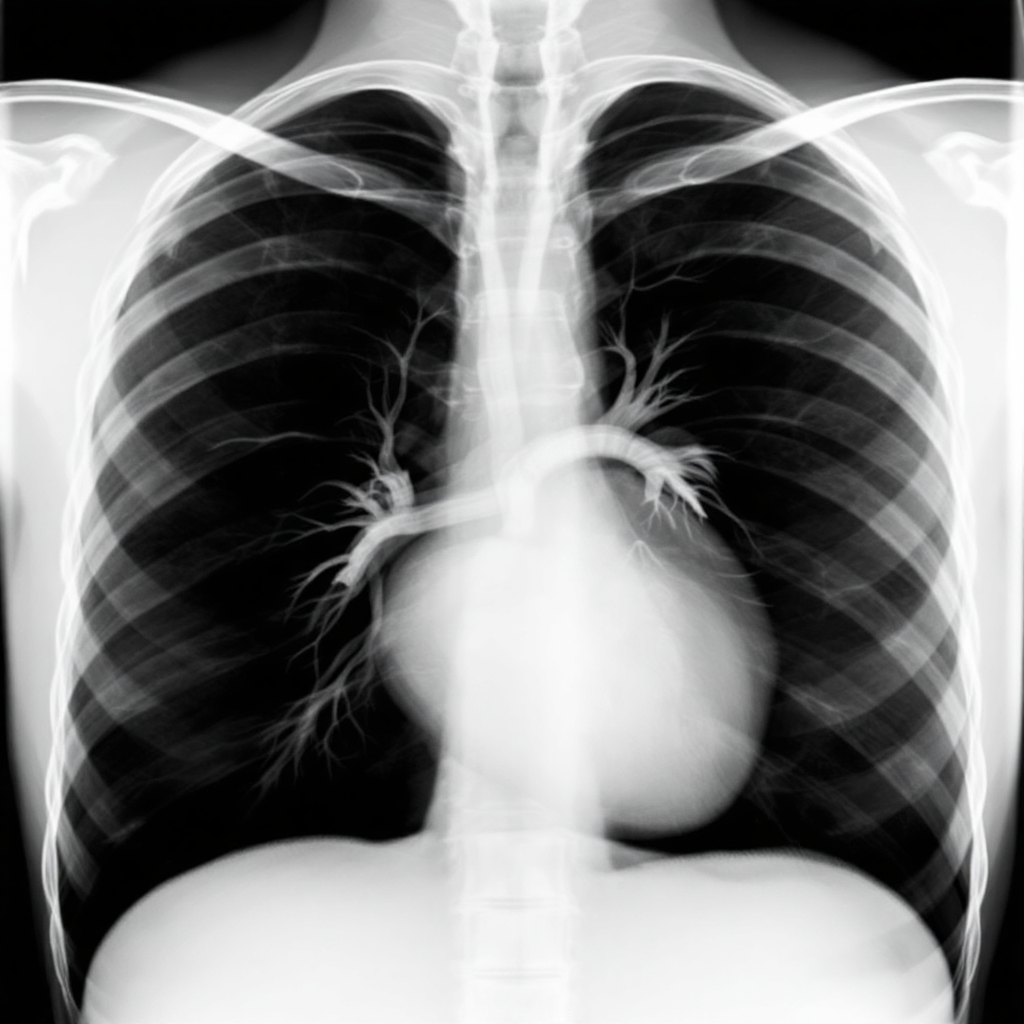

흉막삼출이 의심될 때 첫 단계는 흉부 X-ray 촬영이에요. 특히 측면 엎드린 상태에서 촬영하는 측와 촬영이 흉막강에 고인 액체를 가장 잘 보여줘요.